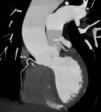

A 74-year-old man, with a history of heavy smoking, presented with unstable angina (Figure 1). Dobutamine stress echocardiography showed ischemia in the right coronary artery territory. Coronary angiography revealed no obstructive epicardial disease in the left dominant circulation (Figure 2A); the right coronary artery (RCA) was a small caliber and tortuous vessel, with only minor atheroma. However, an abnormal vessel arising from the proximal RCA was noted (Figure 2B and C), confirmed as a fistulous connection to the left atrium by multislice computed tomography, which also excluded other vascular anomalies (Figure 3). This was deemed to be causing a coronary steal phenomenon. Exercise myocardial perfusion imaging under anti-ischemic therapy excluded residual ischemia and the patient was successfully conservatively managed (Figure 4).

Given the fistula's small size, from a non-dominant coronary artery, and in the absence of right ventricular impairment or significant ischemic burden, a conservative approach was followed. We highlight the role of multimodality imaging to depict CPAF anatomy and their relationship with relevant cardiac structures, and the role of stress testing in guiding therapy.